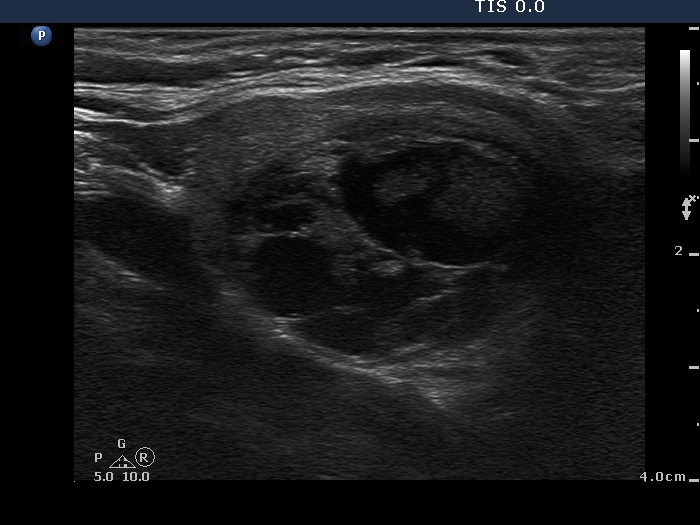

Follicular adenoma (histological diagnosis) - case 108

Almost every cystic chamber presents the back wall posterior enhancement.